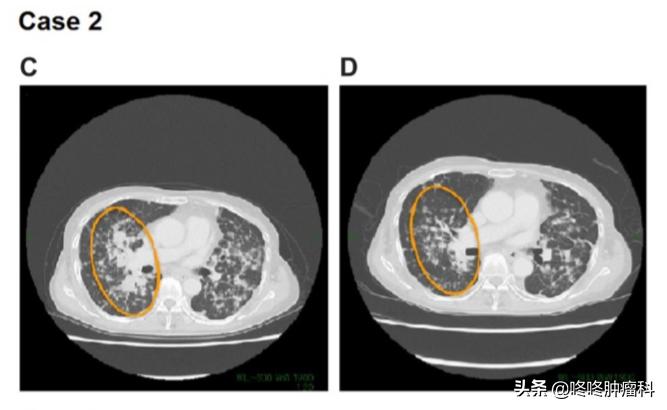

C:2017年12月阿法替尼治疗前评估;D:阿法替尼治疗后于2018年11月评估

在各治疗手段治疗都出现进展下,通过测序检测,发现患者有 CD74-NRG1融合 。患者因此使用上了阿法替尼,在接受阿法替尼治疗11个月后,患者于2018年11月 达到PR 。截止到2020年2月统计时,患者仍在使用阿法替尼,持续PR中。